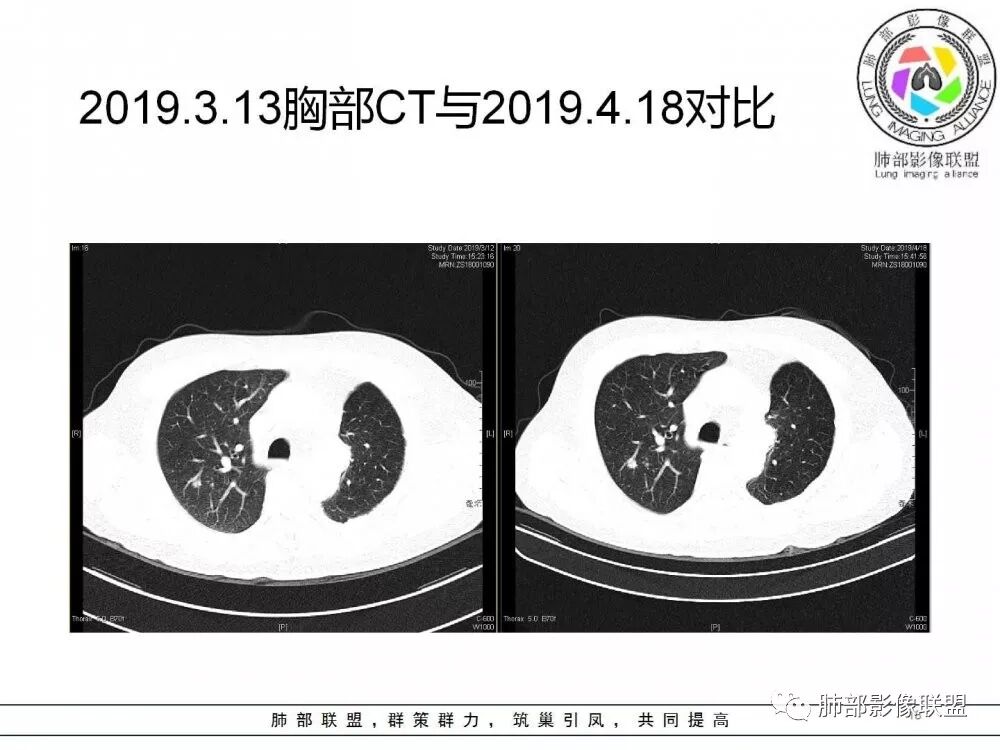

右肺上叶后段实性结节,部分边缘磨玻璃,周围可见多发小结节,病灶逐渐进展,临床有肺癌病史、IgG4相关病变、激素长期使用史,考虑1、隐球菌;2、肺癌复发;3、IgG4相关性肺改变,病变局限,应该不符合。

右肺上叶后段多发实性结节,边缘收缩,葫芦兄弟,临床有激素治疗史,考虑隐球菌。

肺癌病史,长期激素使用史,IgG4相关病史,治疗有抗癌和激素治疗,肺部多发胸膜下小结节,边缘模糊,有些结节有进展,葫芦兄弟,考虑隐球菌。

右肺上叶后段实性结节,周围可见多发小结节,病灶逐渐进展,临床有肺癌病史、IgG4相关病变、激素长期使用史,考虑1、隐球菌;2、肺癌复发;3、IgG4相关性肺改变

肺部病灶从2月份就开始有了,应该最早说是1月7号就有了,到3月13号稍微增大一点,到后面几乎就没变化了,到5月份好像稍微大一些,炎性肯定是炎性,就是这个炎性是到底什么病变呢?其实本没变化,它特点一个是在叶裂上,跟血管关系密切,但是病灶边缘稍收缩,病灶这么没有太大变化,我还是支持炎性病变。